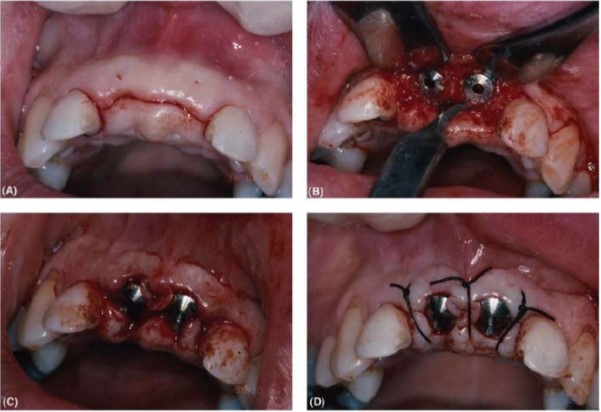

Loạt ảnh lâm sàng minh họa quá trình phẫu thuật đặt abutment. (A) Đường rạch đỉnh sống hàm ngay trên đầu implant kéo dài vào khe nướu răng bên cạnh (B) Bóc tách vạt tốt cho phép lấy bỏ phần xương che phủ vít đậy bằng cây đục cầm tay (C) Vật được điều chỉnh theo trụ lành thương. Mép vạt được tạo hình lại, phần mô thường bị cắt bỏ giờ được giữ lại và ôm xoay quanh trụ lành thương (D) Khâu đóng vạt bằng các mũi khâu rời đơn giản